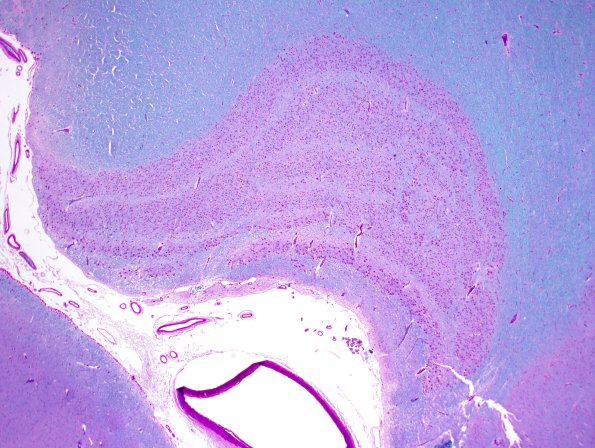

Washington University Experience | NORMAL | Hippocampus & LGN | 1B1-Hippocampus-normal-Case-1-LFB-PAS-2X.jpg

1B1,2 The LGN is laminated which is seen well in this LFB-PAS preparation where myelin separates the lamellae into two ventral magnocellular layers (1 & 2) and 4 dorsal parvicellular layers (layers 3-6). Layers connect with different eyes. Specifically, the contralateral eye projects to layers 1,4, & 6 and the ipsilateral eye innervates layers 2,3 & 5.